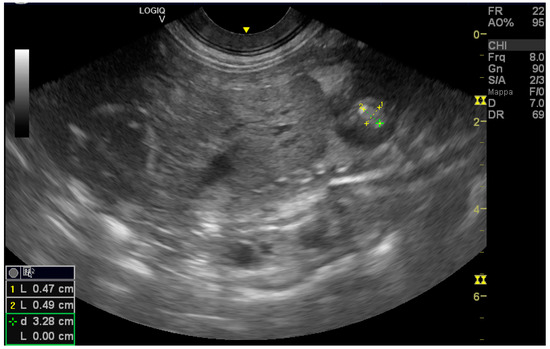

Ultrasound, Histomorphologic, and Immunohistochemical Analysis of a Cardiac Tumor with Increased Purkinje Cells Detected in a Canine Fetus 42 Days into Pregnancy

2. Case Description

2.1. Clinical Findings